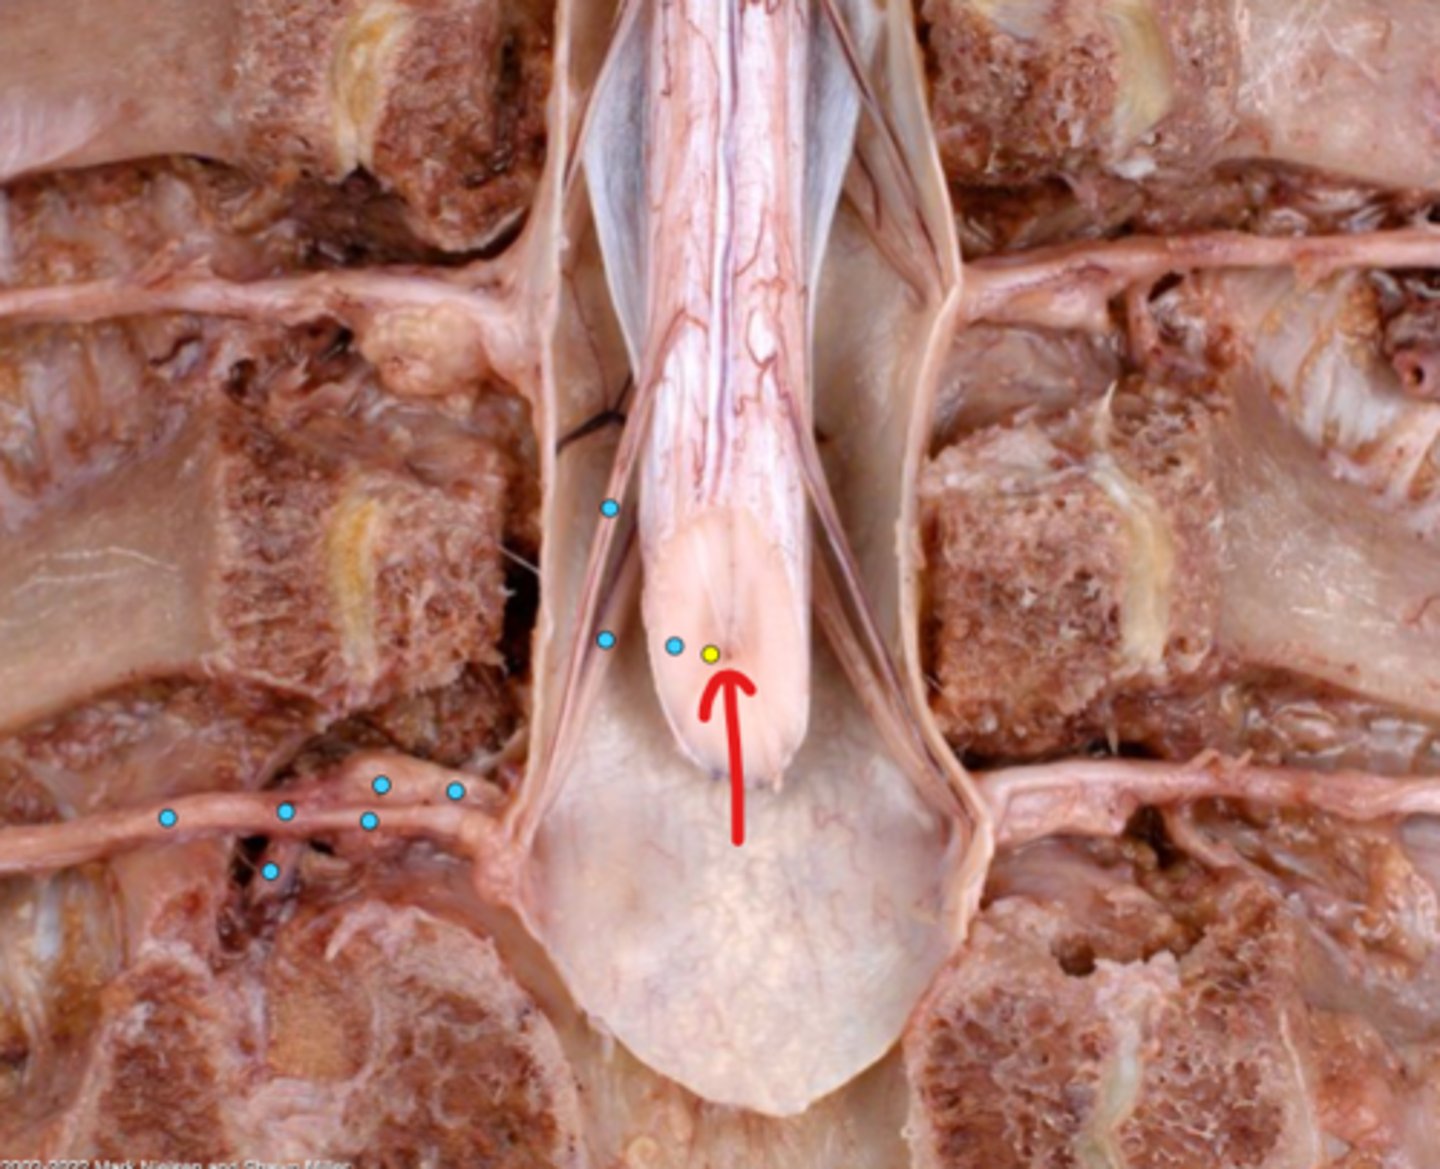

Intercostal nerve

Communicating ramus

Sympathetic trunk ganglion

Sympathetic trunk

Lesser splanchnic nerves

Greater splanchnic nerve

Anterior (ventral) ramus

Spinal nerve trunk

Posterior (dorsal) ramus

Spinal ganglion

Anterior (ventral) root

Posterior (dorsal) root

Anterior (ventral) rootlets

Posterior (dorsal) rootlets

White matter

Gray matter

Posterior (dorsal) rootlets

Anterior (ventral) rootlets

Spinal cord